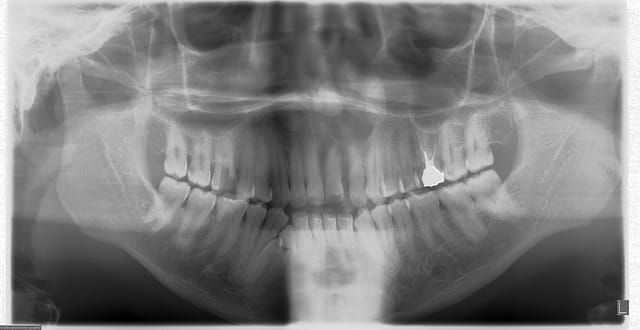

Il s'agit d'un patient africain avec une grosse lacune au dessus de la 22 . A savoir que le patient est en super bipro alveolie.

Asymptomatique totalement. Je sens une grosse dépression a la palpation.

A operer ? a explorer? a surveiller ?

Bonjour, sur ton scan et sur ta pano on ne voit pas de continuité entre les apex et le defect osseux, pourquoi veux tu intervenir au niveau dentaire?

on dirait une lésion des tissus mous.

Le déplacement dentaire indique qu'il y a un processus tumoral sous-jacent, certainement bénin mais y'a quelque chose

après réflexion, ma première hypothèse serait un kyste naso-labial.

on dirait qu il y a des dents surnuméraires ou odontoides:

possible deux dans la lacune au dessus de 22 et voir au dessus de 12... voir 3D

A la palpation je sens une depression importante et pas une voussure c est pour ca que je pensais plus a une lesion idiopathique qu a un kyste congenital . Je vous post les coup antero post des que je suis au cabinet

toujours est-il que la topographie et la sémiologie radiologique sont compatibles avec le KNL.

genre lacune de stafn

genre une lacune de stafne du maxillaire (supérieur) ??? ch'ui pas franchement convaincu et reste sur mon analyse qui correspond à quelquechose qui est décrit même si on l'observe rarement.

j'ai eu 4 cas du genre depuis le début d'année (dont 2 kératokystes (k.épidermoide) très récidivants :< ),j'aurais préféré que tu nous montre les coupes coronales sur ton scan.